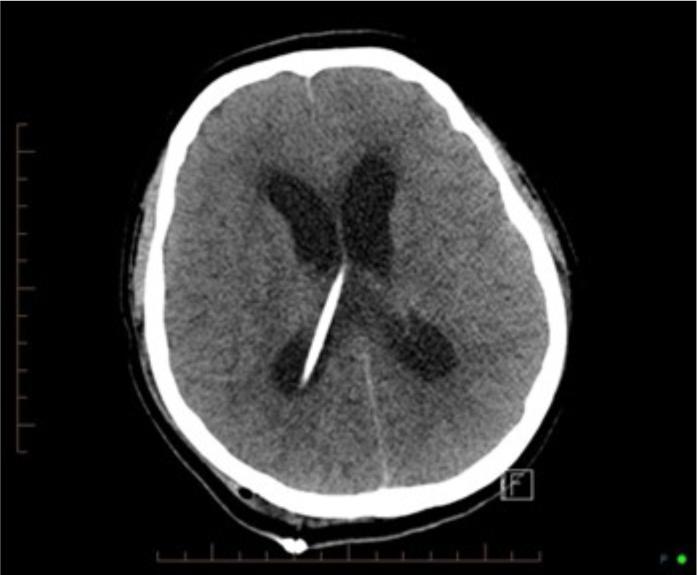

Pictured above is one of the scans the patient had during February showing enlarged ventricles indicative of hydrocephalus from the blocked shunt.

Complications of TBM include obstructive hydrocephalus, caused by the release of a thick exudate from the bacteria which causes blockages in cerebrospinal fluid (CSF) flow (Rock, Olin, Baker, Molitor & Peterson, 2008) leading to neurological deterioration. The fluid from the burst abscesses commonly cause vasculitis which also can lead to cerebral infarction or stroke (Rock, Olin, Baker, Molitor & Peterson, 2008; Man et al., 2010; Sheu et al., 2010; Radwan & Sawaya, 2011.). Vasculitis is inflammation of the blood vessels. This causes them to narrow, leading to loss of perfusion to the brain (NHLBI-NIH, 2014).

Unfortunately, despite the use of dexamethasone, Mr X did develop hydrocephalus, and a VP shunt was inserted. Due to excess protein in the CSF, the shunt continued to block and it was replaced with a short term external ventricular drain (EVD) with the hope that the protein would reduce or a bigger shunt could be found from India, where TB prevalence is higher.